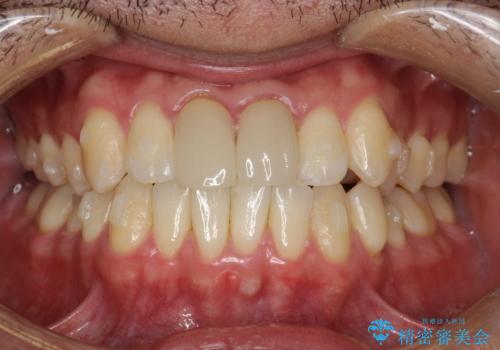

上下のがたつきをインビザラインで目立たない矯正

- 前歯のガタガタを主訴に来院されました。

上下の前歯のガタガタと左上の歯が反対にかんでいる状態でした。

上下の歯と歯の間をわずかに削り並べる計画としました。

目立たずに歯並びがよくなり、前歯に装着されたセラミックも壊さずに矯正治療が終了し満足していただけました。